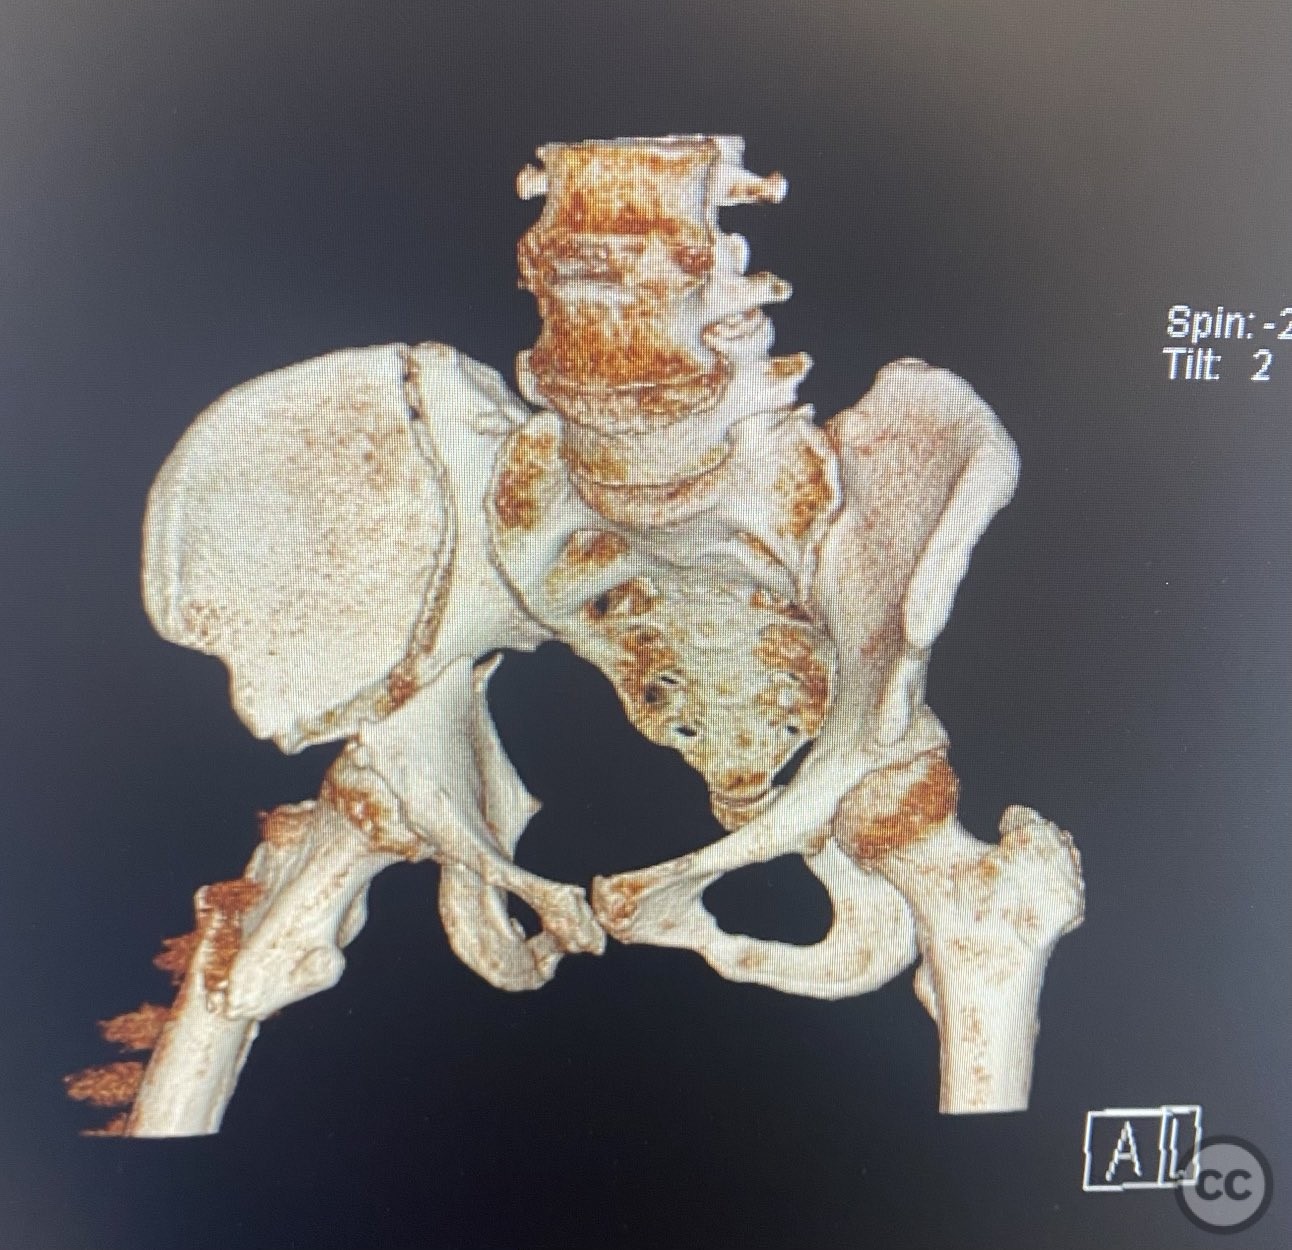

acetabulum fracture

türkiye, Turkey

Pelvis - AO/OTA 6x